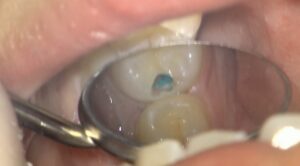

虫歯が見えてきました。

この部分は柔らかくなっており、触るとボロボロ崩れてきます。

虫歯を青く染める検知液も使いながら、

取り残しのないように虫歯になってしまっている部分を削っていきます。

虫歯を取りました。